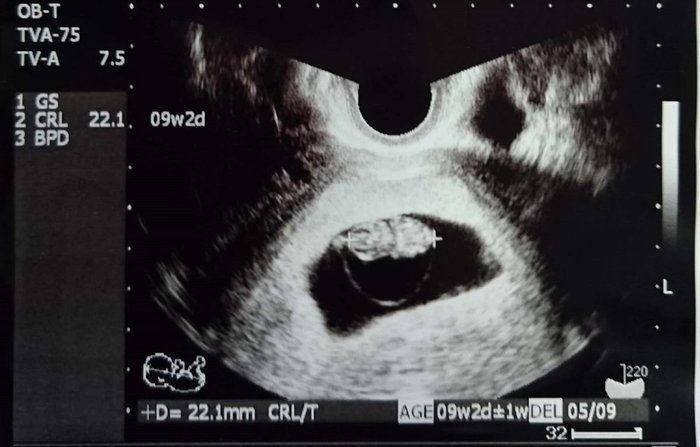

クリコさんの妊娠9週目のエコー写真

4D画像で頭、手、足を見ることができました。枝豆のような頭の形でなんだかかわいい、と早くも親バカ。この時期は、子宮がんや感染症の免疫の有無など、様々な検査を行いました。実母に、私がはしかやおたふく風邪にかかったかなどや、母がどのような妊娠・出産をしたかを教えてもらいました。